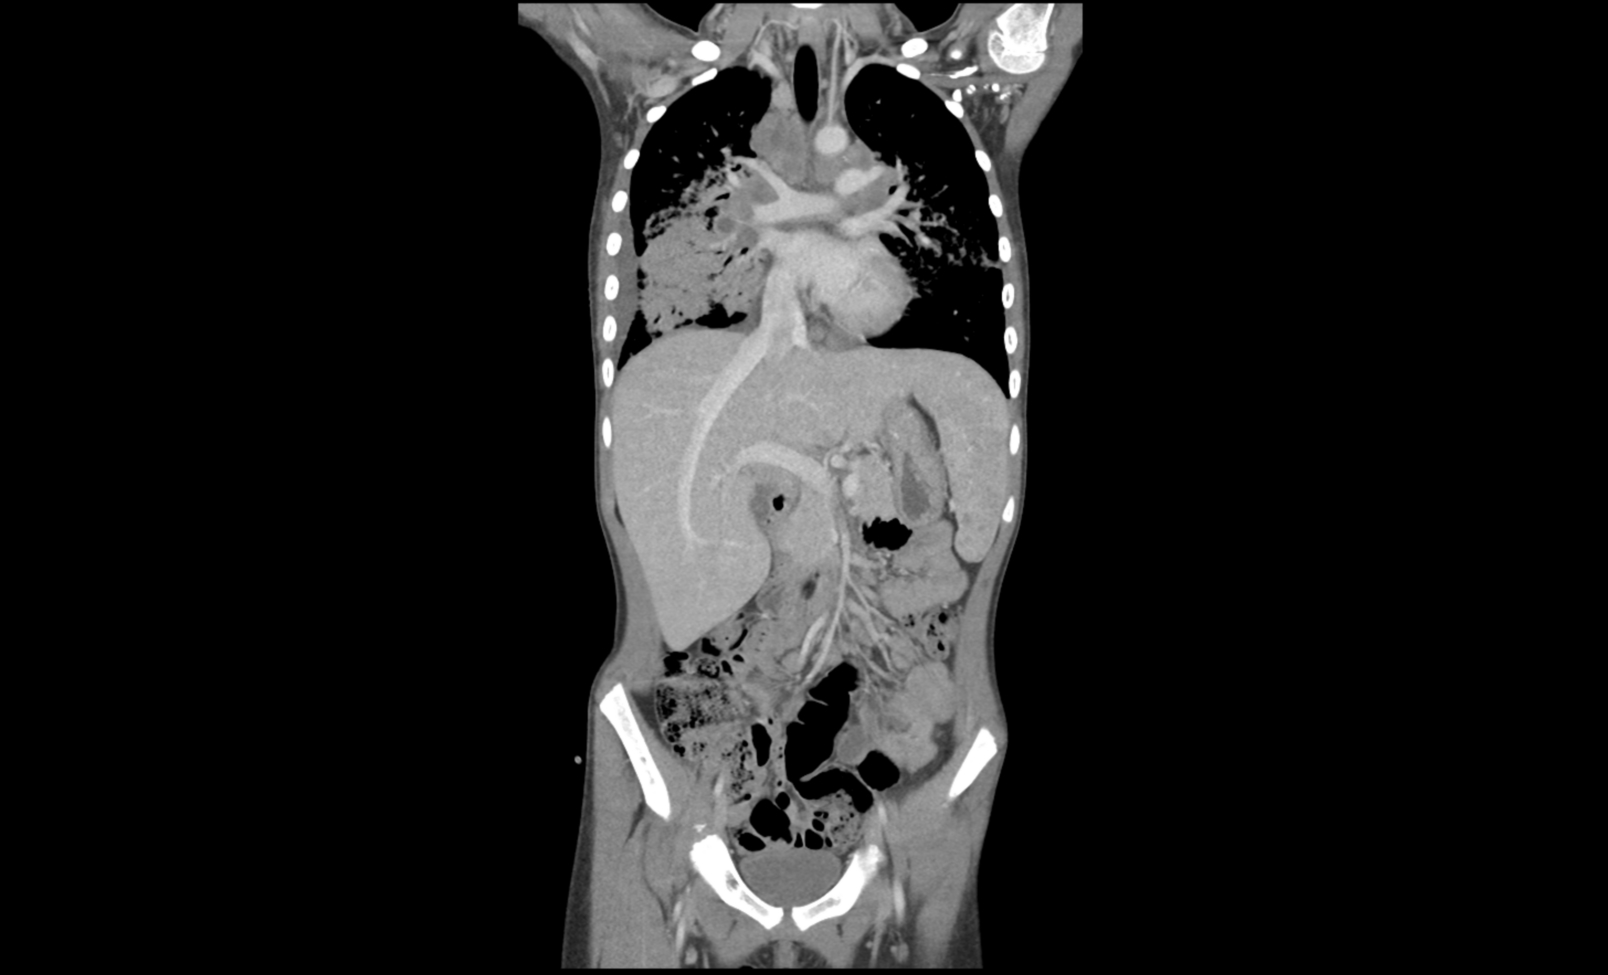

Ante la falta de etiología a filiar y la persistencia de astenia, anorexia, conglomerados adenopáticos y palpación de hepatomegalia, se decide solicitar una tomografía computarizada (TC) toraco-abdomino-pélvica.